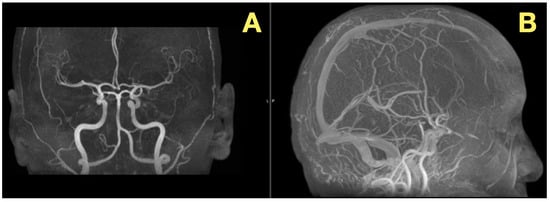

In addition to its rarity, the case also stood out due to the fact that all of the patient’s preoperative angiograms revealed a normal architecture of cerebral vasculature and no indication of aneurisms, arteriovenous malformations, or impaired venous outflow (Figure 2A,B). Further, the Circle of Willis was fully developed and symmetrically distributed, and the dural venous sinuses were unobstructed. As such, these studies ruled out vascular-related causes of intracranial hypertension and were consistent with a slowly expanding, avascular lesion.

Figure 2. Preoperative vascular imaging. (A): Frontal MRA maximum-intensity projection: normal configuration of the circle of Willis without aneurysm or stenosis (B): Lateral MRA: preserved arterial flow and patent dural venous sinuses, excluding vascular or venous causes of intracranial hypertension; the pressure increase is attributable to CSF-outflow obstruction by the fourth-ventricular mass.